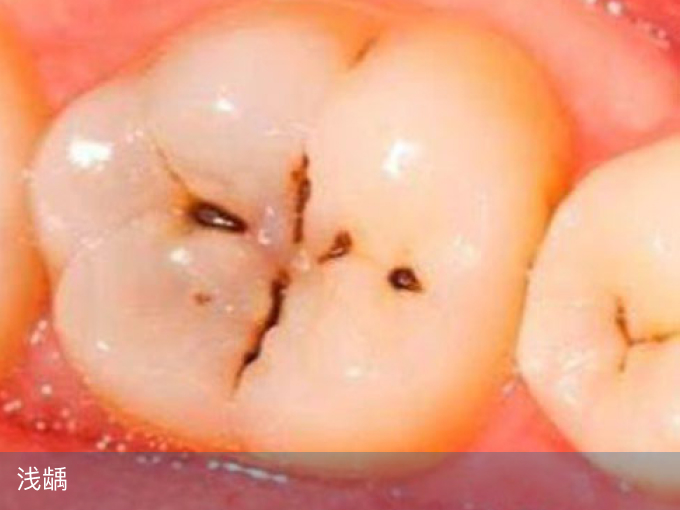

1、浅龋

此时的龋坏仅涉及牙釉质,如果只出现黑色素沉积,探针无法探入,可以不补,早晚按时刷牙即可保持在静止龋状态。如果探针可探入,则建议进行补牙,根据补牙材质、所在地消费水平不同,一颗牙在100-400元之间。